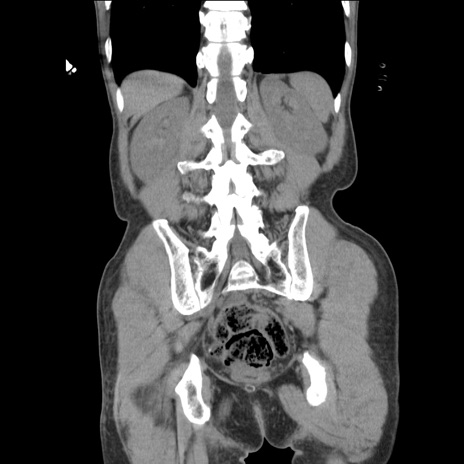

症例11(冠状断像)

【症例】 60歳代男性

【主訴】 下腹部痛

【現病歴】 本日夜中より下腹部痛の症状認め、受診。

【既往歴】 膀胱癌(膀胱全摘+尿管皮膚瘻術) 、胃癌術後

【身体所見】 BT 35.3℃、PR 58/min、BP 136/98mHg、腹部平坦、軟、腸蠕動音±、ストマ留置あり、左上腹部~正中部に圧痛あり、反跳痛なし。

【データ】WBC 5100、CRP0.01